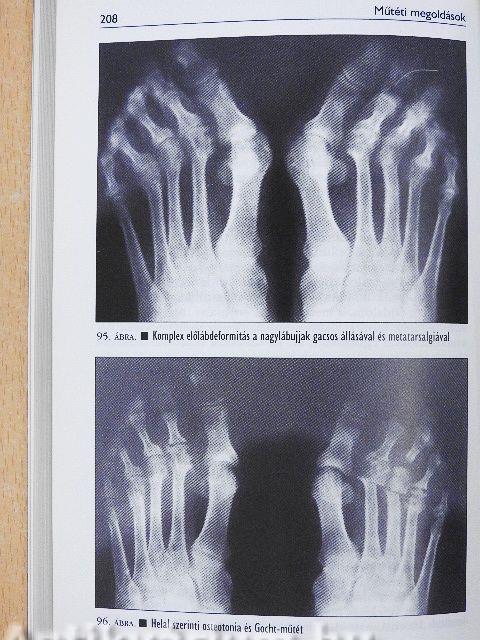

A komplex előlábdeformitások műtétei206

Metatarsalgia207